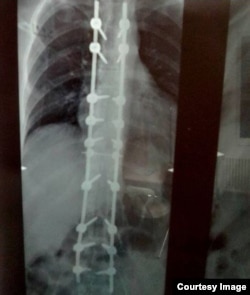

У Евгения из Алтайского края болезнь Бехтерева, поражающая позвоночник и грозящая неподвижностью. В 2018 году ему сделали операцию, установили на позвоночник титановую конструкцию, но лечение может лишь замедлять болезнь и повышать качество жизни. Евгению необходимо ежедневно несколько часов носить корсет полужёсткой фиксации с двумя металлическими пластинами, но его у него нет до сих пор.

Рентген-снимок позвоночника Евгения

– В 2021 году областной Фонд социального страхования заключил контракт на поставку корсетов с московской компанией "Стан", – рассказывает Евгений. – Когда я обратился в фонд с вопросом о корсете (сейчас на поставку ТСР по закону отводится месяц), мне сказали, что поставщик оказался очень непорядочный и не исполняет свои обязанности. В январе 2023-го я опять обратился – уже в Социальный фонд России (СФР), получил такой же ответ. В марте 2023-го написал заявление в прокуратуру. Прокуратура меня поддержала, подала в суд. Последнее заседание прошло 25 июля, решение было принято в мою пользу, но сдвигов пока нет.

– Я не знаю, связано это с отсутствием средств или просто бюрократия. Но у меня на позвоночнике металлоконструкция, 18 болтов, естественно, мне ежедневно надо носить корсет по нескольку часов, чтобы облегчить нагрузку на позвоночник. И альтернативы у меня нет. Без корсета у меня прогрессирует болезнь, постоянно нахожусь дома.